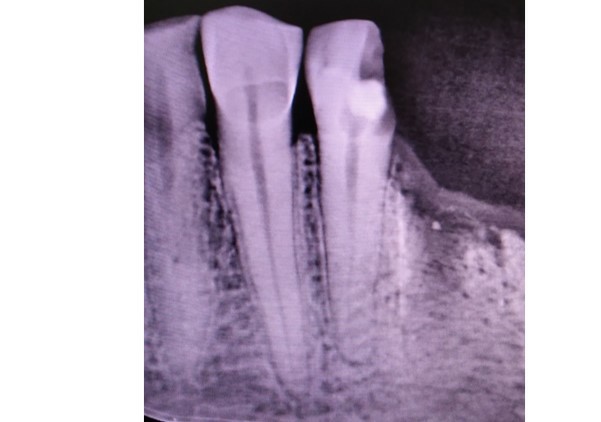

Root canal treatment with crown restoration

Complex endodontic case